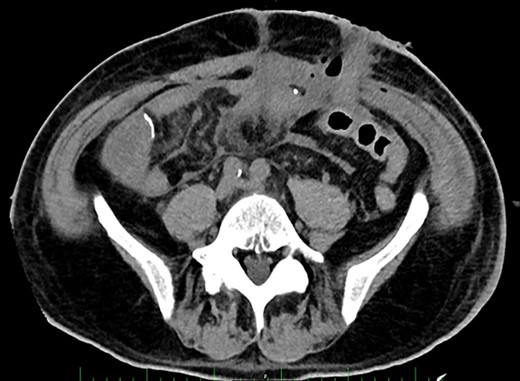

Post-operative Day 20. Abdominal CT-scan with free intraperitoneal fluid, without sign of ileus, perforation or anastomosis release.

On Days 19 and 20, the patient reported no pain, with only transient febrile episodes at 38.1°C during the night. Abdominal examination was normal, and stomas, wall VAC and dressings (which were repeated daily under sedation) did not show any issues. CRP and WBC counts were stable. In contrast to the apparent clinically stable picture, PSP dosing showed elevated concentrations of 392 ng/ml and >600 ng/ml on Days 19 and 20 respectively. Based on this, a new abdominal CT-scan was performed and showed several intraperitoneal fluid collections of radiological density suggestive of an intra-abdominal infection (Fig. 3). The patient was returned to the operating room and surgery confirmed intra-abdominal infection and post-operative peritonitis with purulent collections (cultures will show E. coli 48 h later). An intraperitoneal lavage was performed, the abdomen was kept open and a laparostomy using VAC with continuous intraperitoneal lavage was put into place.